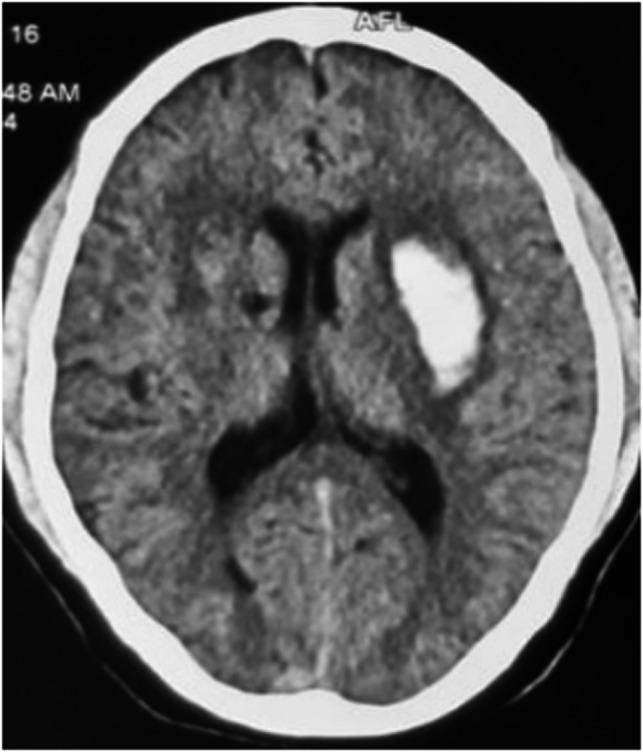

Hypertension is the most prevalent determinant condition embarking on the development of spontaneous intracerebral hemorrhage. Usually, the presentation is a unilateral hematoma. Spontaneous bilateral intracerebral hemorrhage is an outstandingly infrequent context, and not a lot of cases have been reported till date. Ensuing hypertension, trauma inflicted on the brain case is another common cause that out turn into the sequelae of bilateral intracerebral hemorrhage. Lately, a few cases of bilateral basal ganglia bleed have been revealed, as a repercussion of COVID-19 infection. Globally, <40 such cases have been reported. A 39-year-old man presented with complaints of acute onset of weakness of right half of the body. Additionally, facial deviation was noticed by his family members. He then sought medical help from a local healthcare center where CT scan of head was advised. Unexpectedly, the scan demonstrated bilateral intracerebral hemorrhage. He was then managed conservatively with oral medications and rehabilitation. The course of his hospital stay was uneventful and was eventually discharged after 9 days. He then presented to our institution for further evaluation. Thereupon, he had slurring of speech but was able to walk with minimal support. Simultaneous Bilateral Basal Ganglia Hemorrhage (SBBGH) is an exceptionally rare ailment. This genre of cerebrovascular accident embraces a comprehensive span of morbidity and mortality. In an acute setting, CT scan of head is the most relevant imaging modality. Nonetheless, MRI is the gold standard for definitive diagnosis and should be performed urgently to further typify and delineate the lesion.

高血压是自发性脑出血发展过程中最常见的决定性因素。通常,表现为单侧血肿。自发性双侧脑出血极为罕见,迄今为止报道的病例不多。继高血压之后,脑外伤是导致双侧脑出血后遗症的另一个常见原因。最近,有几例双侧基底节出血病例被发现,是新冠病毒感染的后果。全球范围内,已报道的此类病例不到40例。一名39岁男性因右侧身体急性无力前来就诊。此外,其家人发现他有面部偏斜。随后他前往当地医疗中心寻求帮助,在那里医生建议对头进行CT扫描。出乎意料的是,扫描显示双侧脑出血。随后他接受了口服药物保守治疗和康复治疗。他住院期间病情平稳,9天后最终出院。然后他到我们机构进行进一步评估。当时,他说话含糊不清,但在极少的帮助下能够行走。同时性双侧基底节出血(SBBGH)是一种极其罕见的疾病。这种类型的脑血管意外涵盖了广泛的发病率和死亡率。在急性情况下,头部CT扫描是最相关的影像学检查方法。尽管如此,MRI是明确诊断的金标准,应紧急进行以进一步明确和描绘病变。